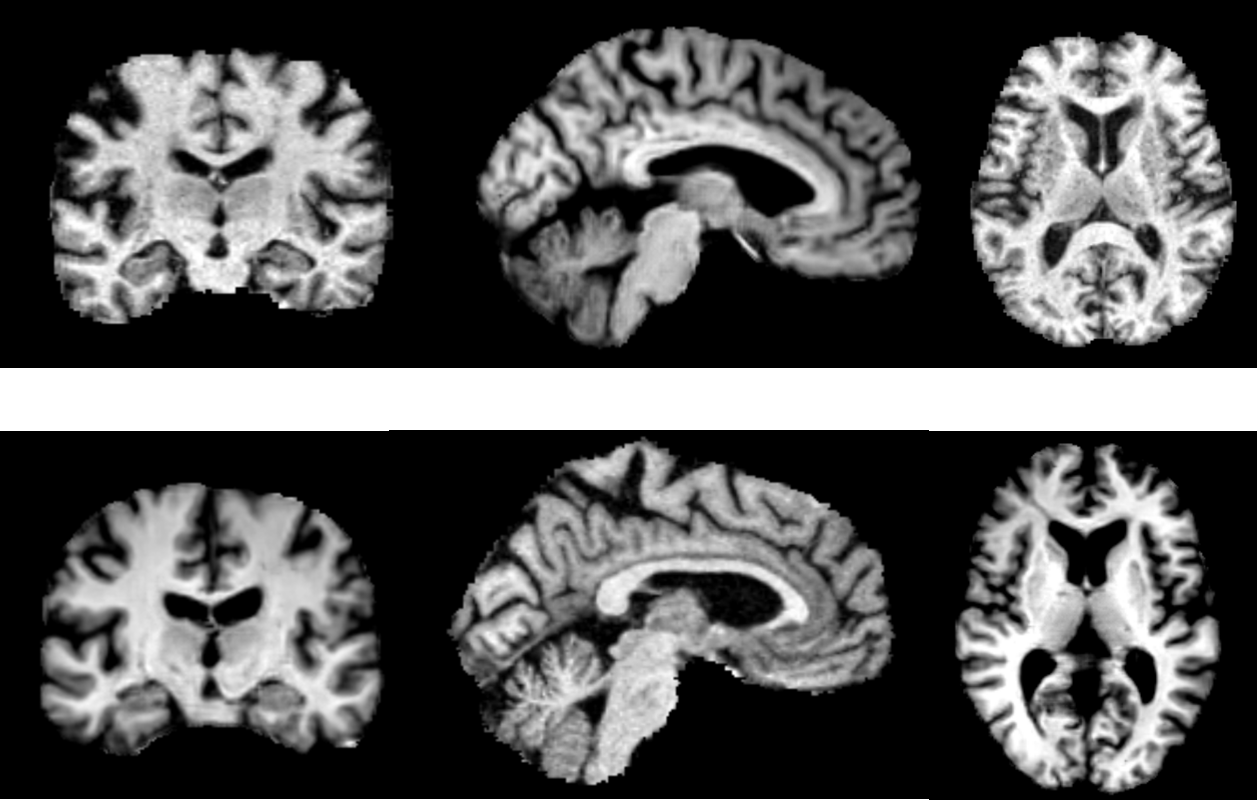

General synthesized image evaluation We evaluate the synthesised images by Fréchet Inception Distance (FID) and Maximum Mean Discrepancy (MMD). Lower values of FID/MMD indicate that the distributions of synthesised images are closer to real ones. As shown in Table 2, our model is compared with the state-of-the-art 3D image generator HA-GAN [15] and a styleGAN model by Hong et al. [21]. Since they use different metrics, we take the numbers they report and compare our model with them, respectively. Figure 3(b) shows a sample and more are presented in the supplementary material. The results prove our model can generate realistic images comparable with the-state-of-art model. We also request a clinician with over 30 years of brain image reading experience to recognize if an image is real or synthesized for 50 randomly selected images. His recognition accuracy is 50%, exactly like flipping a fair coin.

(b) Real and sampled MRI

Figure 3: (a) The joint distribution of score and ventricle volume. Negative correlation can be observed. (b) Real MRI (the first row) and synthesized MRI (the second row) sampled from our generator.